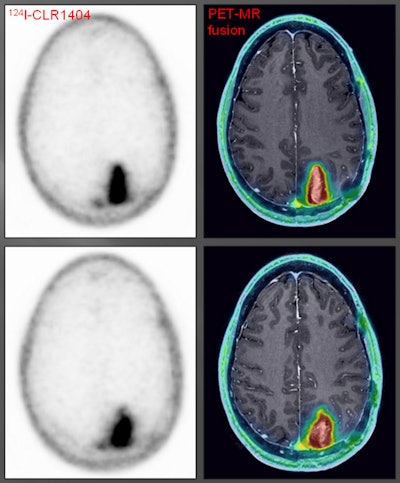

Image comparisons

The subjects were injected with 2 to 5 mCi (74 to 185 MBq) of CLR1404 and imaged with PET/CT six hours, 24 hours, and 48 hours after injection. Fourteen patients were followed until surgery or with gadolinium-enhanced MRI for six months or longer.

The researchers found avid CLR1404 uptake in 12 of the 16 patients; four individuals with cancer recurrence (as opposed to pseudoprogression) had no tracer uptake. There was no significant uptake of CLR1404 in normal areas of the brain and no uptake in regions that were treated for cancer and were presumably tumor-free.

CLR1404-PET successfully imaged tumors with high tumor-to-background uptake and uncovered larger tumor volumes than contrast-enhanced MRI.

"We saw areas of concordant and discordant PET uptake and MRI enhancement," Hall said. "This is what we are really excited about, those discordant areas. Those are the areas where we have the ability to add perhaps more accurate complementary information to what MRI shows."